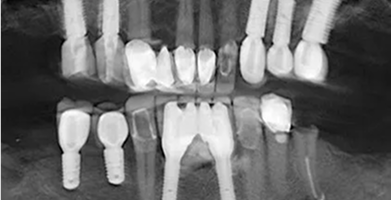

Multiple Implants

Used to restore several missing teeth or support a full arch restoration.

BEFORE

AFTER